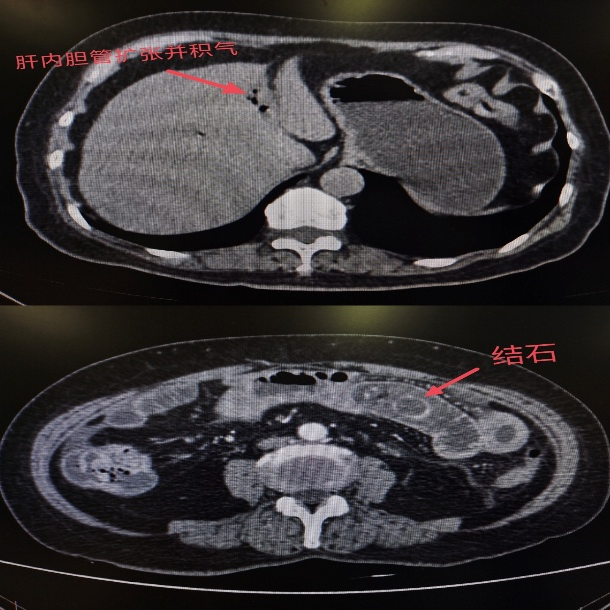

随后腹部CT检查结果显示:李阿姨的胆囊已经发生穿孔,一枚结石从破口处掉进小肠,并牢牢卡在肠腔内,形成了机械性肠梗阻。 更严重的是,由于结石嵌顿时间较长,已导致局部肠壁明显水肿、炎症。